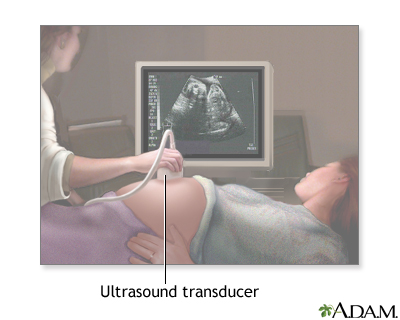

Procedure, part 1

As you lie on an exam table, a sonographer coats your belly with a slick -- and possibly cold -- gel. Next, he moves a transducer, a hand-held device shaped like a microphone, over your belly. You can see the resulting images on a nearby computer screen.